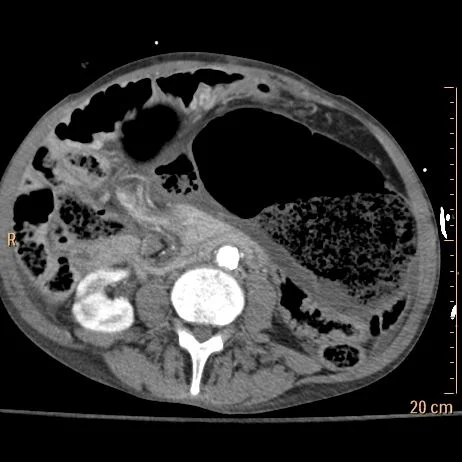

55 yo F with abdominal distention and vomiting. Conventional CT shows distended and malpositioned cecum and ascending colon, with a mesenteric swirl. On spectral analysis, note lack of perfusion in the distended colon and terminal ileum.

Conventional CT with dilated malpositioned cecum